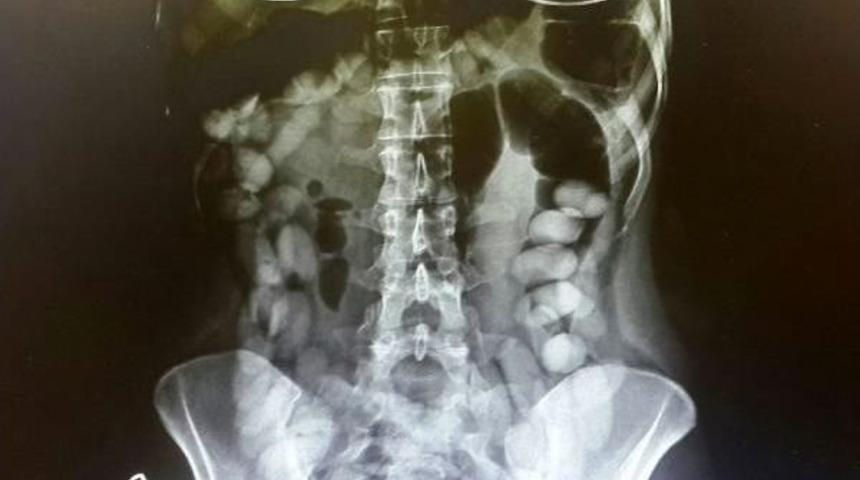

- İSVİÇRE'nin Zürih kentinden uçakla Antalya'ya gelen Venezuela uyruklu 29 yaşındaki M.S.R. adlı kadının midesinde, her biri 10-12 gram ağırlığında 78 kokain kapsülü tespit edildi.

27 Eylül günü Zürih- Antalya seferini yapan uçakla kente gelen Venezuela uyruklu M.S.R. adlı kadının uyuşturucu madde kuryesi olabileceği istihbaratı üzerine polis harekete geçti. M.S.R., uçaktan indikten sonra gözaltına alındı. Yapılan iç muayenesinde, midesinde çok sayıda yabancı cisim olduğu görülen M.S.R., hastanede gözetim altına alındı. Kadının midesinde, her biri 10-12 gram ağırlığında 78 kokain kapsülü tespit edildi. Şu ana kadar 71 kapsülün doğal yollarla çıkartıldığı kaydedildi.